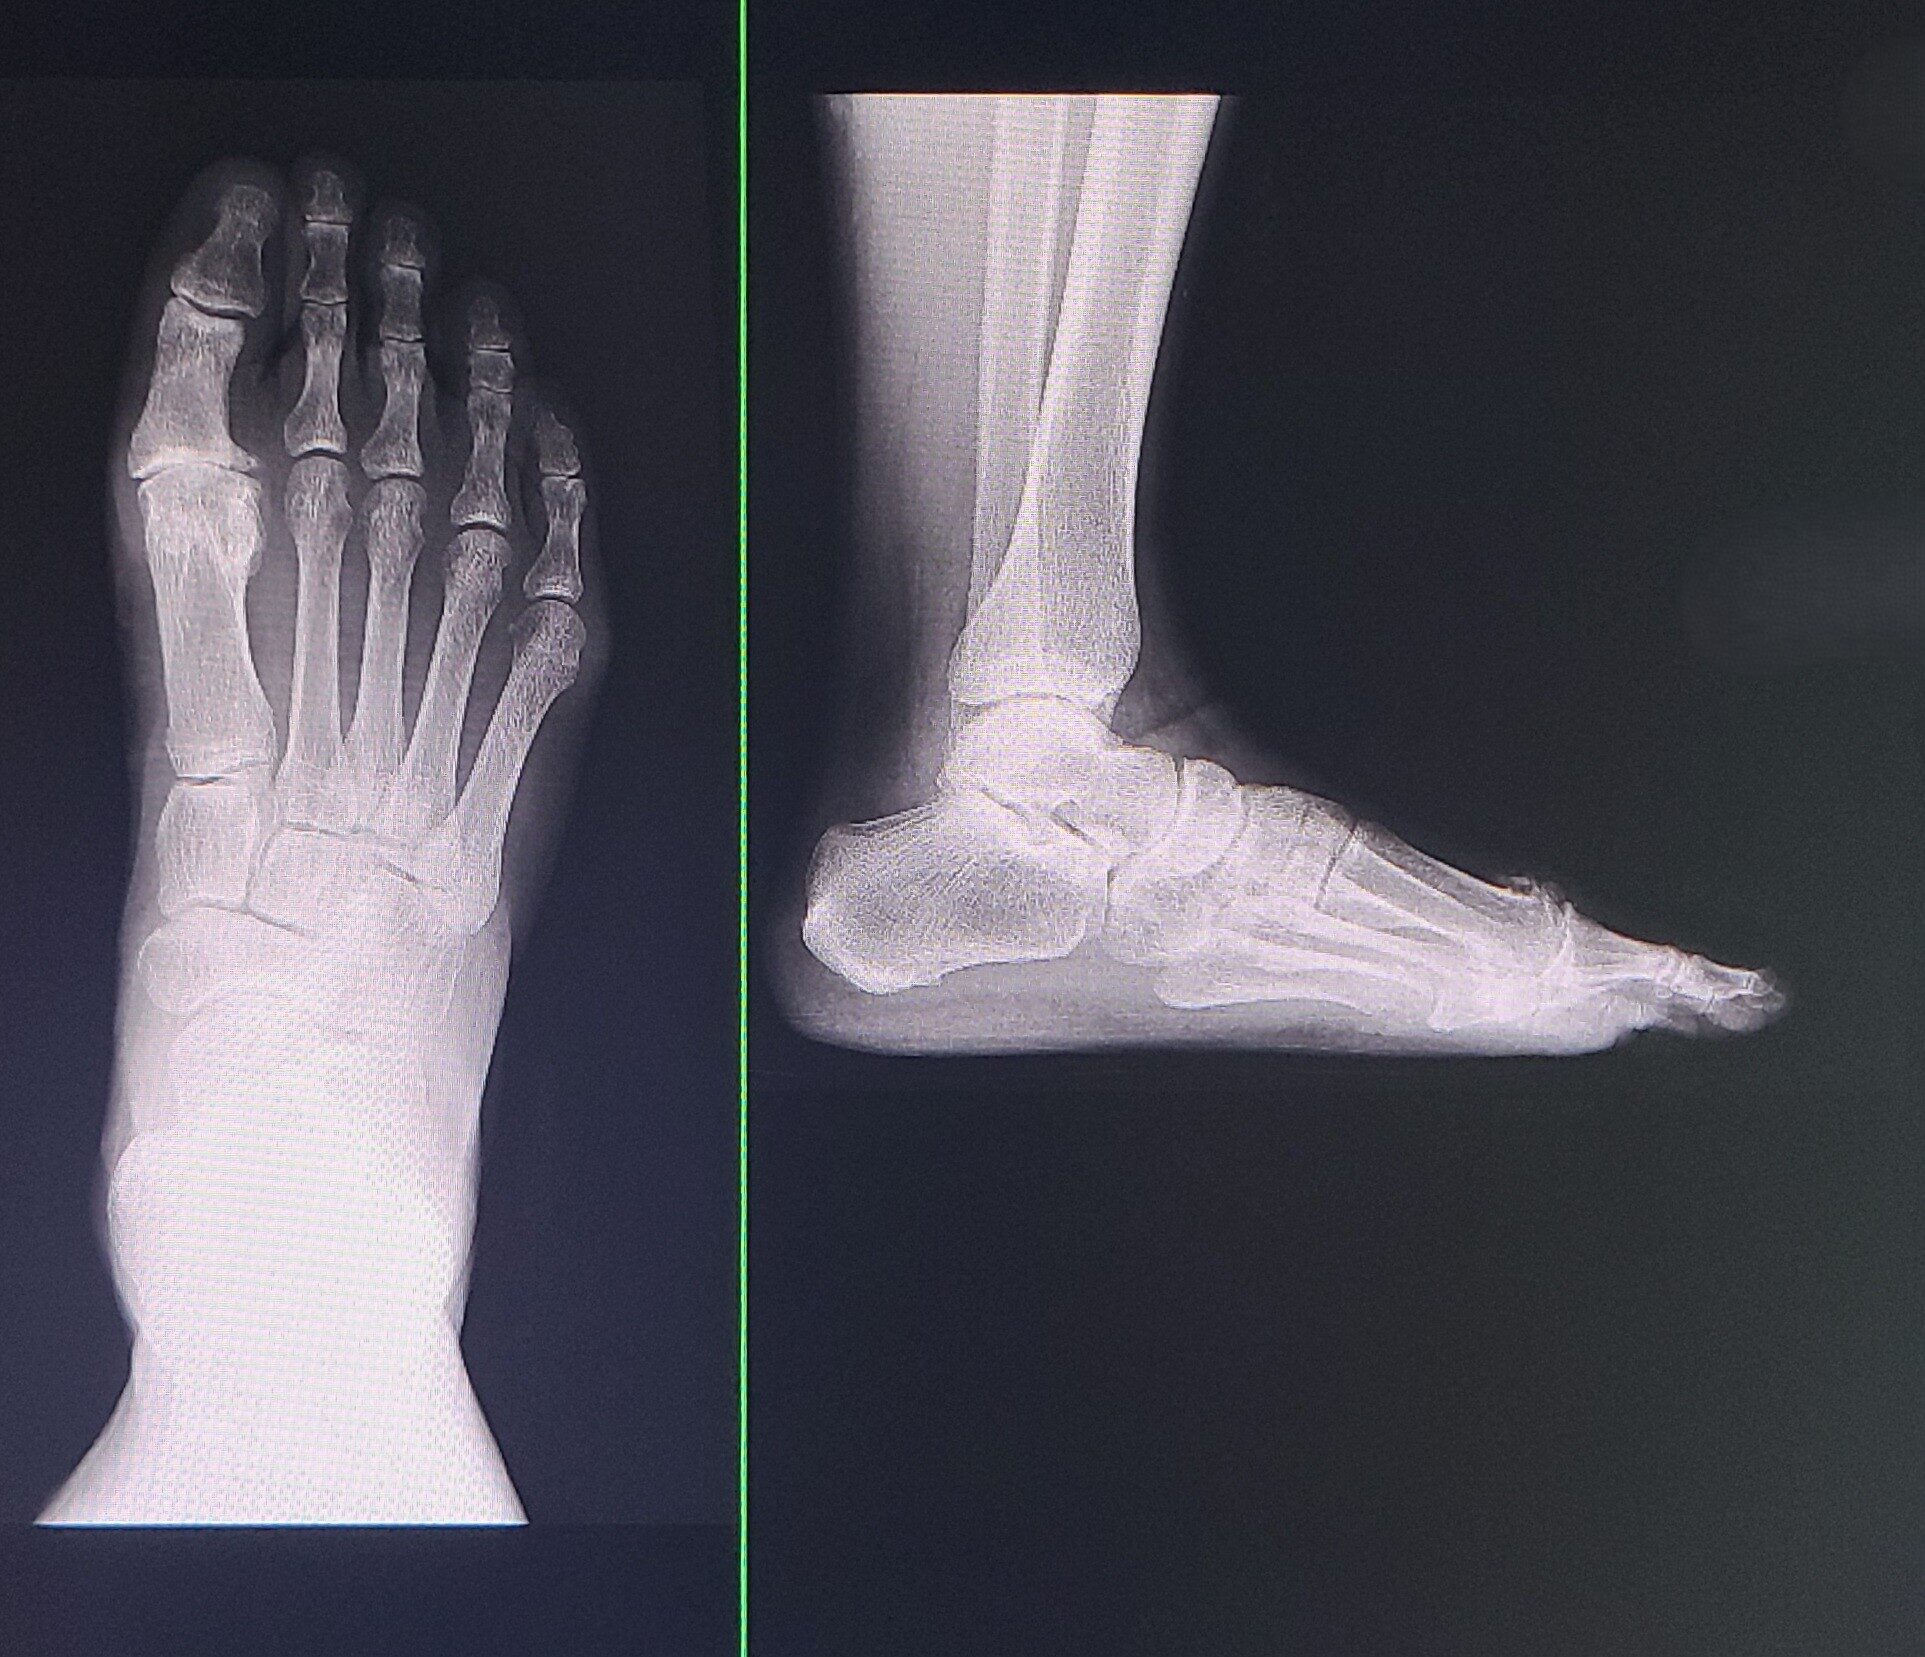

強剛母趾において中足骨(母趾の手前にある骨)が挙上していることが指摘されていますが、まだ一定の見解がありません。以前強剛母趾のレビューの論文を書いているとき、これに関する論文がまだ不足していることがわかりましたので、調べて書こうと思っています。

2025-9-17:Excelの表の整理。今回は片方が強剛母趾で片方が正常の人で左右を比較する予定なので、片方のみ手術した人をピックアップする作業。結果270人ほどに。文献のExcelの表作成。文献検索。早速病院で10人ほど計測したが、ここで躓いた。中足骨が上がっているといってもほんの数ミリの話なので、精度の高い測定をしないと有意な差として現れない。測定前は測定の軟部組織の境界線と思っていたが、境界があいまいで簡単に数ミリの誤差が出てしまう。これはほかの文献を読んだり、出す結果を違うものにしたりしないとだめだ。

2025-10-21:文献読み。まとめの表に記入。計測方法はいくつかあるが、多くの研究で用いられているのは主に2つ。ここはあまりに奇抜な計測法を採用してもその信憑性を問われそうだから、「過去の文献と同様にしました」とした方がすんなり受け入れられそう。むしろそのほかの部分(症例数、健側患側間での比較、グレード間の比較)を売りにした方がよさそう。

その2つの指標でレントゲンを計測したら、10例くらい測ったところでつまづいた。片足が強剛母趾でもう片足が正常な足の症例で比較論文を書こうと思ったが、あまりに多くの人が両足とも強剛母趾なのである。これだと異常に症例数が少なくなってしまう。両足強剛母趾例も含める?方針変更が必要だ。

2025-11-14:最近まで他の論文の執筆や査読や学会発表や参考書の分担部分の執筆などで忙しかったが、やっと落ち着いたので、またこちらの論文作成に戻ろう。片足強剛母趾で片足正常な人はほとんどいないので、両足の比較という企画はやめ、手術した足のみのレントゲン写真を入れることにしよう。しかも手術していない足はCTを撮影していないので、病期の確認の時に不備が出てしまう。片足だけにしても250足くらいはデータがあるので十分だろう。第一中足骨の挙上の指標は過去の指標に従おう。